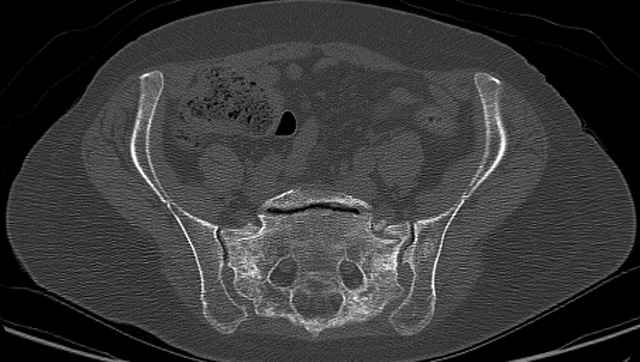

Here are a recent patient’s example slides...

3 Months After Fall

Continued Pain & Immobility

(+) Instability to Compressive Manual Exam

Pelvic CT Scan - 3 Months After Fall

Sacral Injuries

Ramus Fractures